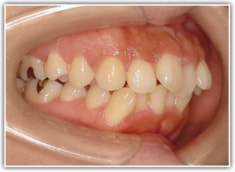

上顎前突ケース

治療法:表の矯正(T21ブラケット)

治療前